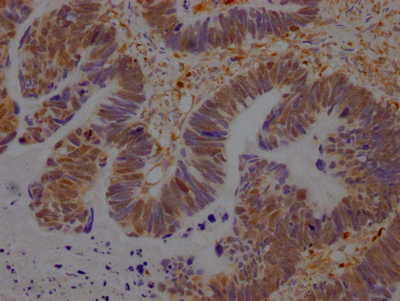

IHC image of CSB-RA981267A0HU diluted at 1:100 and staining in paraffin-embedded human ovarian cancer performed on a Leica BondTM system. After dewaxing and hydration, antigen retrieval was mediated by high pressure in a citrate buffer (pH 6.0). Section was blocked with 10% normal goat serum 30min at RT. Then primary antibody (1% BSA) was incubated at 4℃ overnight. The primary is detected by a Goat anti-rabbit IgG polymer labeled by HRP and visualized using 0.05% DAB.